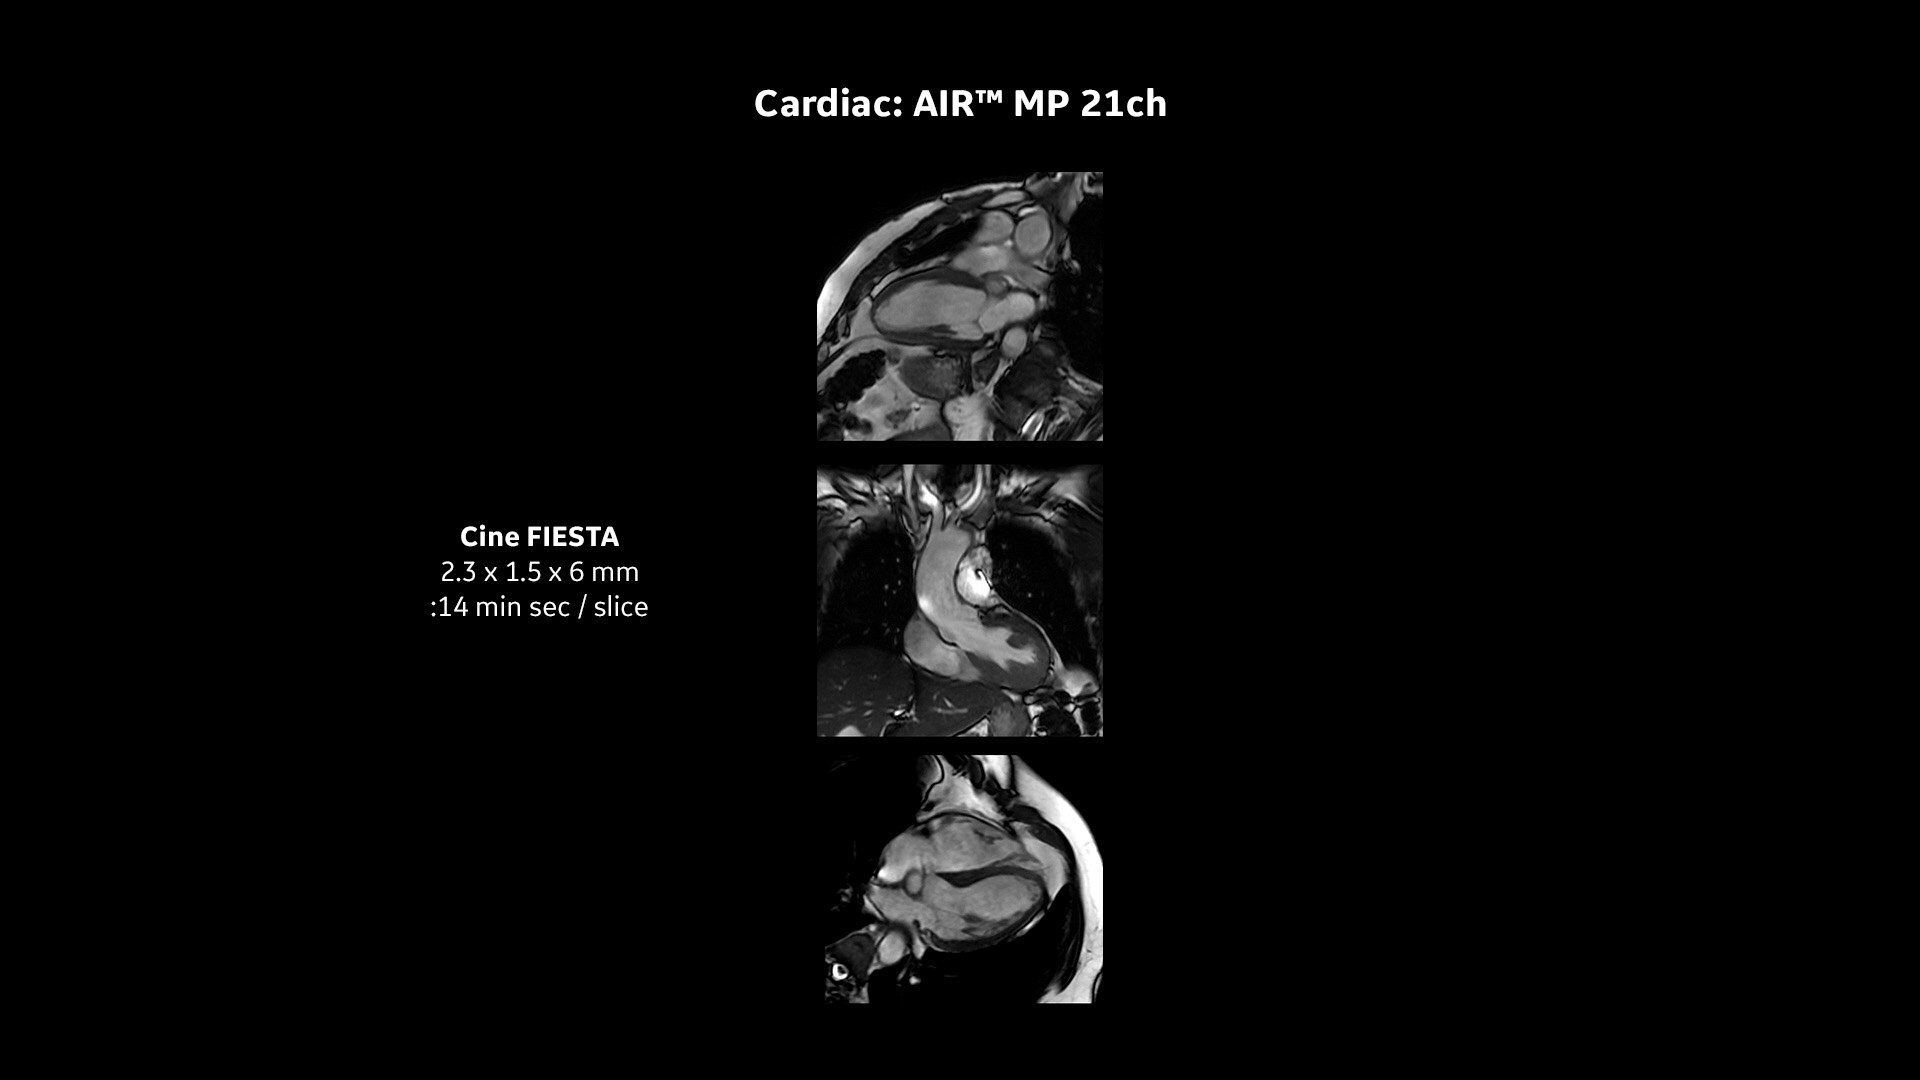

COILS

Pioneering innovations: Intelligent coil technology

Transform the patient experience with our industry-leading AIR™ Coils – the closest you can get to total positioning freedom. They are 50% lighter than conventional coil technology and do not need to be strapped around patients, reducing their anxiety and putting them at ease.

Due to their close positioning, AIR™ Coils can also optimize workflow, boost image quality and reduce exam time which is better for technologists too. Combined with AIR Touch™, a smart recognition software which selects the best coil and element configuration for every scan, all users can ensure consistent results every time.